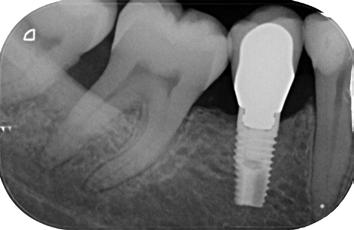

15. ábra: Az irreverzibilis pulpitissel diagnosztizált alsó nagyőrlőfogról készült kiindulási felvétel.

16. ábra: A kezelés közben készült felvétel. Az endodonciai csonkfelépítés már befejeződött, a hozzáférési nyílás kialakításra került és a csatornák előzetes feltágítása is megtörtént. A fogbélkamra alján jól megfigyelhető a transzlucensebb optikai tulajdonságokkal rendelkező pulpakő jelenléte. – 17. ábra: A pulpakövet kézi exkavátorral emeltük ki az üregből. 18. ábra: Az eltávolított pulpakő. – 19. ábra: A pulpakamra alja a gyökértömés elkészítését követően. A pulpakő eltávolítása után a fogbélkamra alja sokkal opakabb képet mutat.

20. ábra: Posztoperatív röntgenfelvétel.

21. ábra: Kiindulási felvétel. Az elhalt felső nagyőrlőfog rágás során panaszokat okoz a páciens számára. A felvételen jól látható a gyökércsatorna-rendszer beszűkültsége.

22. ábra: A hozzáférési nyílás kialakítását követően láthatóvá vált a fényes és kalcifikálódott dentinréteg. – 23. ábra: A kalcifikálódott terület vizsgálata során két gyökércsatorna-bemenet pozícióját sikerült lokalizálni. A kalcifikálódott szöveteket el kell távolítani a csatornák további tágítása előtt. – 24. ábra: A kalcifikálódott szövetek eltávolítását 15/.04-es MicroOpenerrel végeztük. A kalcifikáció néhány milliméter mélyen a palatinális csatornába is beterjedt. – 25. ábra: A pulpakamra aljának képe a csatornák feltágítását követően. A pulpakő eltávolítását követően helyreállt a fogbélkamra aljának megszokott opak megjelenése.

33. ábra: Posztoperatív felvétel.

26. ábra: Posztoperatív röntgen.